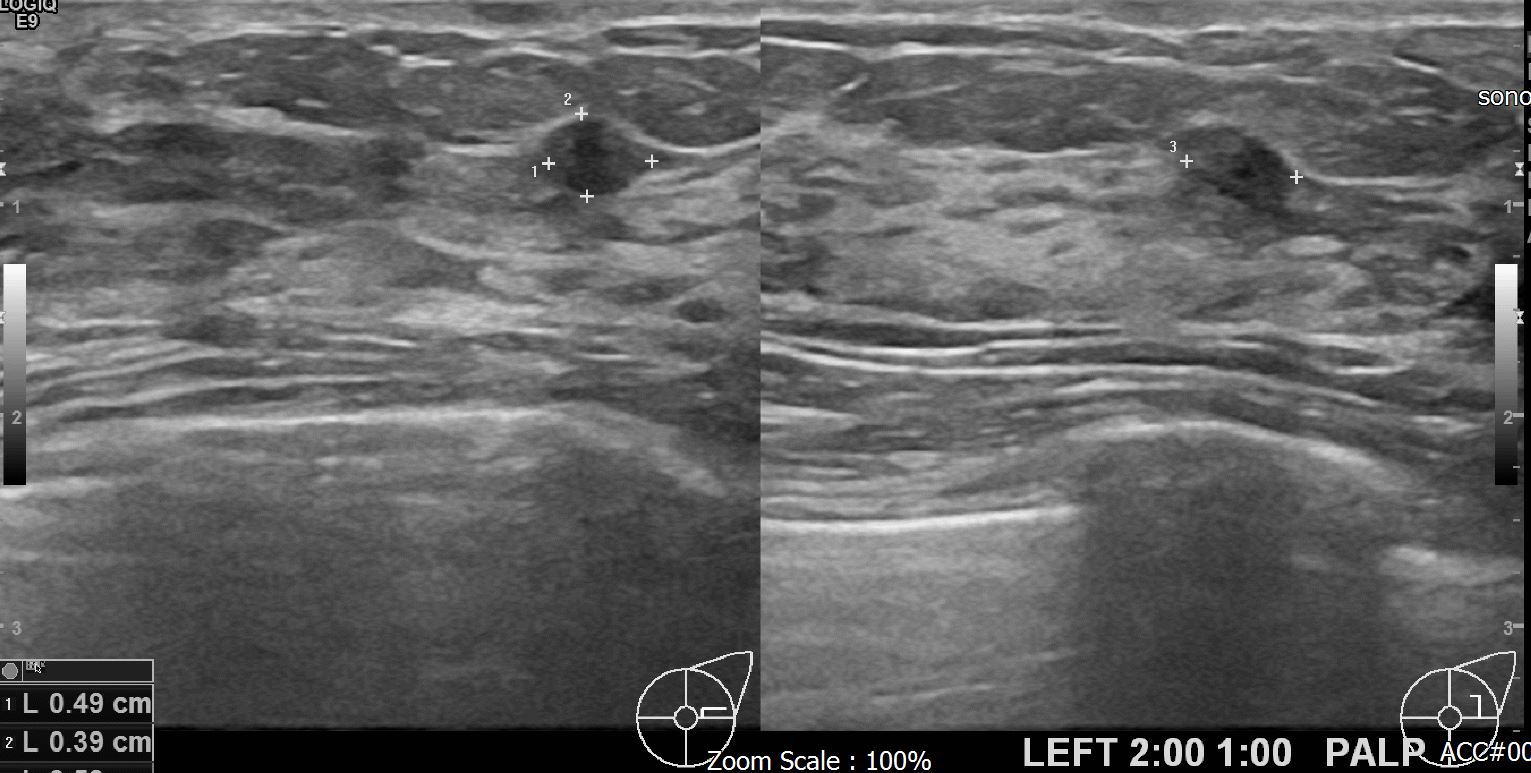

아산유외과 개원후 620번째 유방암 진단

상기 환자 외부검사상 이상소견으로 내원하신 30대 여성분으로 좌측에 의심스러운 혹 조직검사 시행후 유방암 진단 되었습니다.